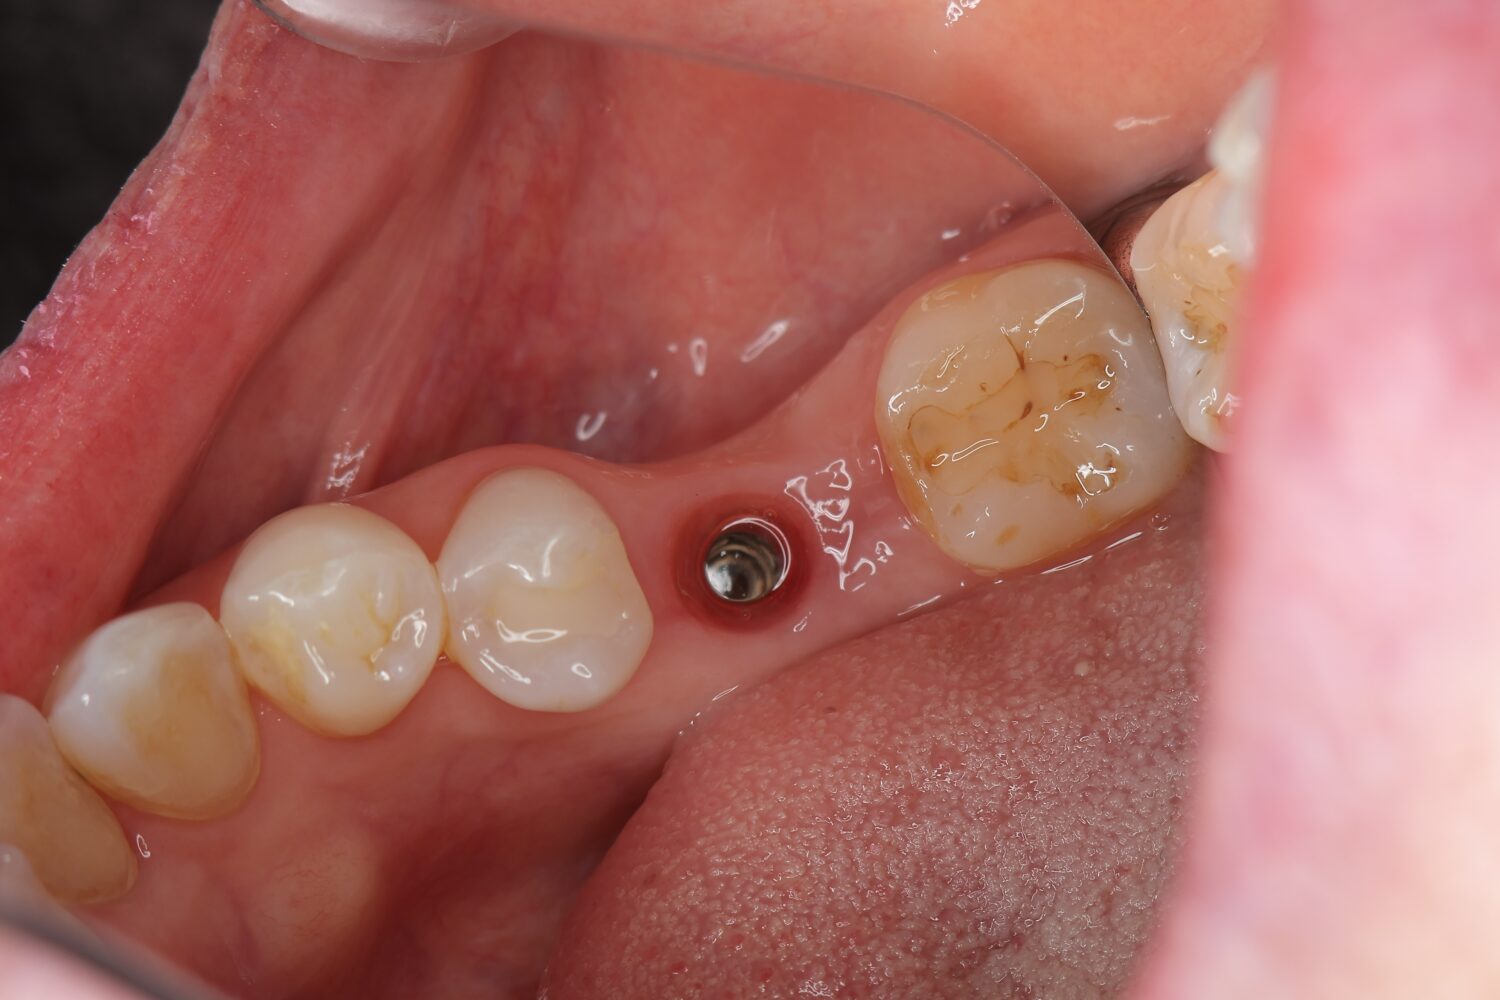

2)治癒期間|骨とインプラントの結合を待ちます

インプラント埋入後は、骨とインプラントが結合するまで治癒期間を設けます。

この期間は、無理な力がかからないように注意しながら、歯ぐきや周囲組織の回復を確認します。

▲ 治癒期間:骨との結合を待っている状態